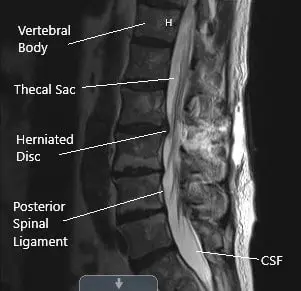

Preoperative Axial MRI section at the L2-L3 level showing herniated disc.

Physical examination corroborated with the imaging studies and the femoral traction test was positive. MRI imaging revealed diffuse disc bulge at L2-L3 and superimposed right paracentral disc herniation. A sequestrated disc herniation in the right lateral recess impinging the descending right L3 nerve root. There are a mild spinal canal and mild bilateral foraminal stenosis.